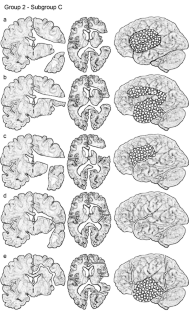

Fig. 2

Fig. 3 a–e